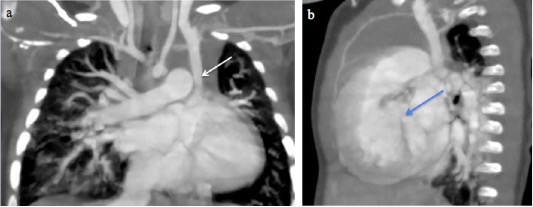

The Figures 1–3 highlight the spectrum of systemic venous anomalies encountered in this study, including a persistent left superior vena cava (PLSVC), a right superior vena cava draining into the left atrium, and a retroaortic left innominate vein, along with their associated cardiac anomalies.

Fig. 1 A 10-month-male infant with Tetralogy of Fallot. a) CT Pulmonary angiography and Coronal Maximum Intensity Projection (MIP) image shows a persistent left superior vena cava (white arrow). b) Coronal MIP image shows a ventricular septal defect (blue arrow).

Fig. 2 A 14-year-old boy with a right superior vena cava draining into the left atrium. (a-c) Sequential axial MIP images from cranial to caudal levels show the right SVC (white arrow) draining into the left atrium (red arrow). Left brachiocephalic vein is also seen (yellow arrow).